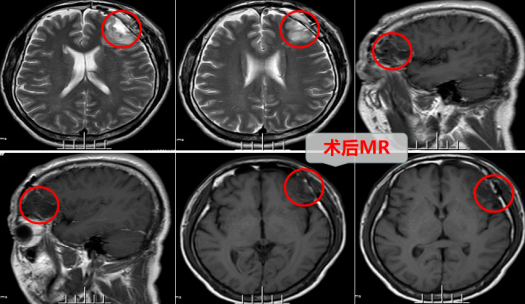

患者住院后神经外十科欧阳辉主任团队很快为他安排详细相关检查,MRI检查结果示:左侧额叶局部皮层及皮层下异常信号影,结合DWI、ASL及MRS,考虑肿瘤性病变,局限性星形细胞胶质瘤可能性大。

医疗团队经过详细病情讨论,决定手术治疗。采用神经外科显微技术行左侧额叶低级别胶质瘤切除术,术中精细雕刻式操作,既完全切除了肿瘤,又完整保护了神经功能。左侧大脑是优势半球,左额叶有诸多重要功能区,医生细致操作,术中功能区均保护完好无损。

术后苏大哥很快苏醒,恢复良好,手脚麻利,也未出现癫痫等不适,高兴的是1年前的症状也消失不见了。